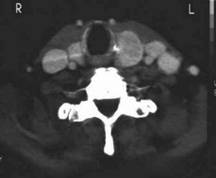

Carcinom paratiroidIAN

Barbat de 56 ani. Carcinom paratiroidian voluminos (44x35x41mm, 31 cc) in paratiroida inferioara dreapta.

CT – acelasi pacient:masa neomogena paratiroida dr. Cu deplasarea traheei spre stanga.